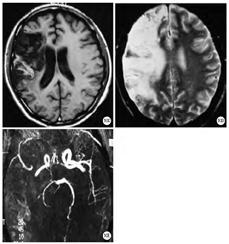

病理改变:弓形虫脑炎的病理特征为形成多发脓肿性疾病,最常累及大脑皮髓质交界处和大脑基底核部位,也可累及脑干、小脑,偶尔累及脊髓。主要是脑组织多灶性坏死,病灶中心神经细胞变性坏死消失,周围血管充血,伴淋巴细胞浸润和小胶质细胞增生,边缘部位较易查见弓形虫假囊和游离速殖子(滋养体)(图3A、图3B)。

影像表现:MR T1WI上病变为低强度信号,T2WI病灶为中等强度信号,周围水肿带为高强度信号,静脉内注射对比剂(Gd-DTPA)后,病灶本身呈高信号,而水肿带不增强(图3C、图3D)。影像检查也用于弓形虫的疗效评估等[5]。

病理改变:隐球菌在中枢神经系统主要累及脑膜组织及大脑的基底部。肉眼可见软组织肿胀,软脑膜浑浊,脑沟内有胶样组织聚集。内含单核细胞,淋巴细胞和大量的隐球菌包子;也可见巨噬细胞增生,小灶性肉芽肿形成。肉芽肿样病变导致动脉血栓形成和多灶性皮质梗死、出血,并可扩大为隐球菌脓肿,形成占位。镜下可见隐球菌包子(图7A、图7B)。

影像表现:MR检查一般无特异性表现。仅见因交通性脑积水引起的脑室扩张及轻度脑萎缩,增强扫描可见脑基底底部脑膜强化,与低信号的脑组织形成良好的对比。如果大脑的基底部形成虫蚀样多发小囊肿,MRI呈长T1长T2信号(图7C、图7D),如果有隐球菌脓肿形成,形成占位,特别在基底节区平扫呈囊状和蜂房状,长T1长T2信号,周围脑组织水肿也呈长T1长T2信号。较特异的表现为脑基底部V-R间隙增宽,但需排除其他V-R间隙增宽的疾病[11]。增强后显示环状和蜂窝状强化(图7C,图7D,图7E,图7F,图7G,图7H)。血清及脑脊液中隐球菌荚膜多糖抗原的检测,能够诊断神经系统隐球菌感染[12]。